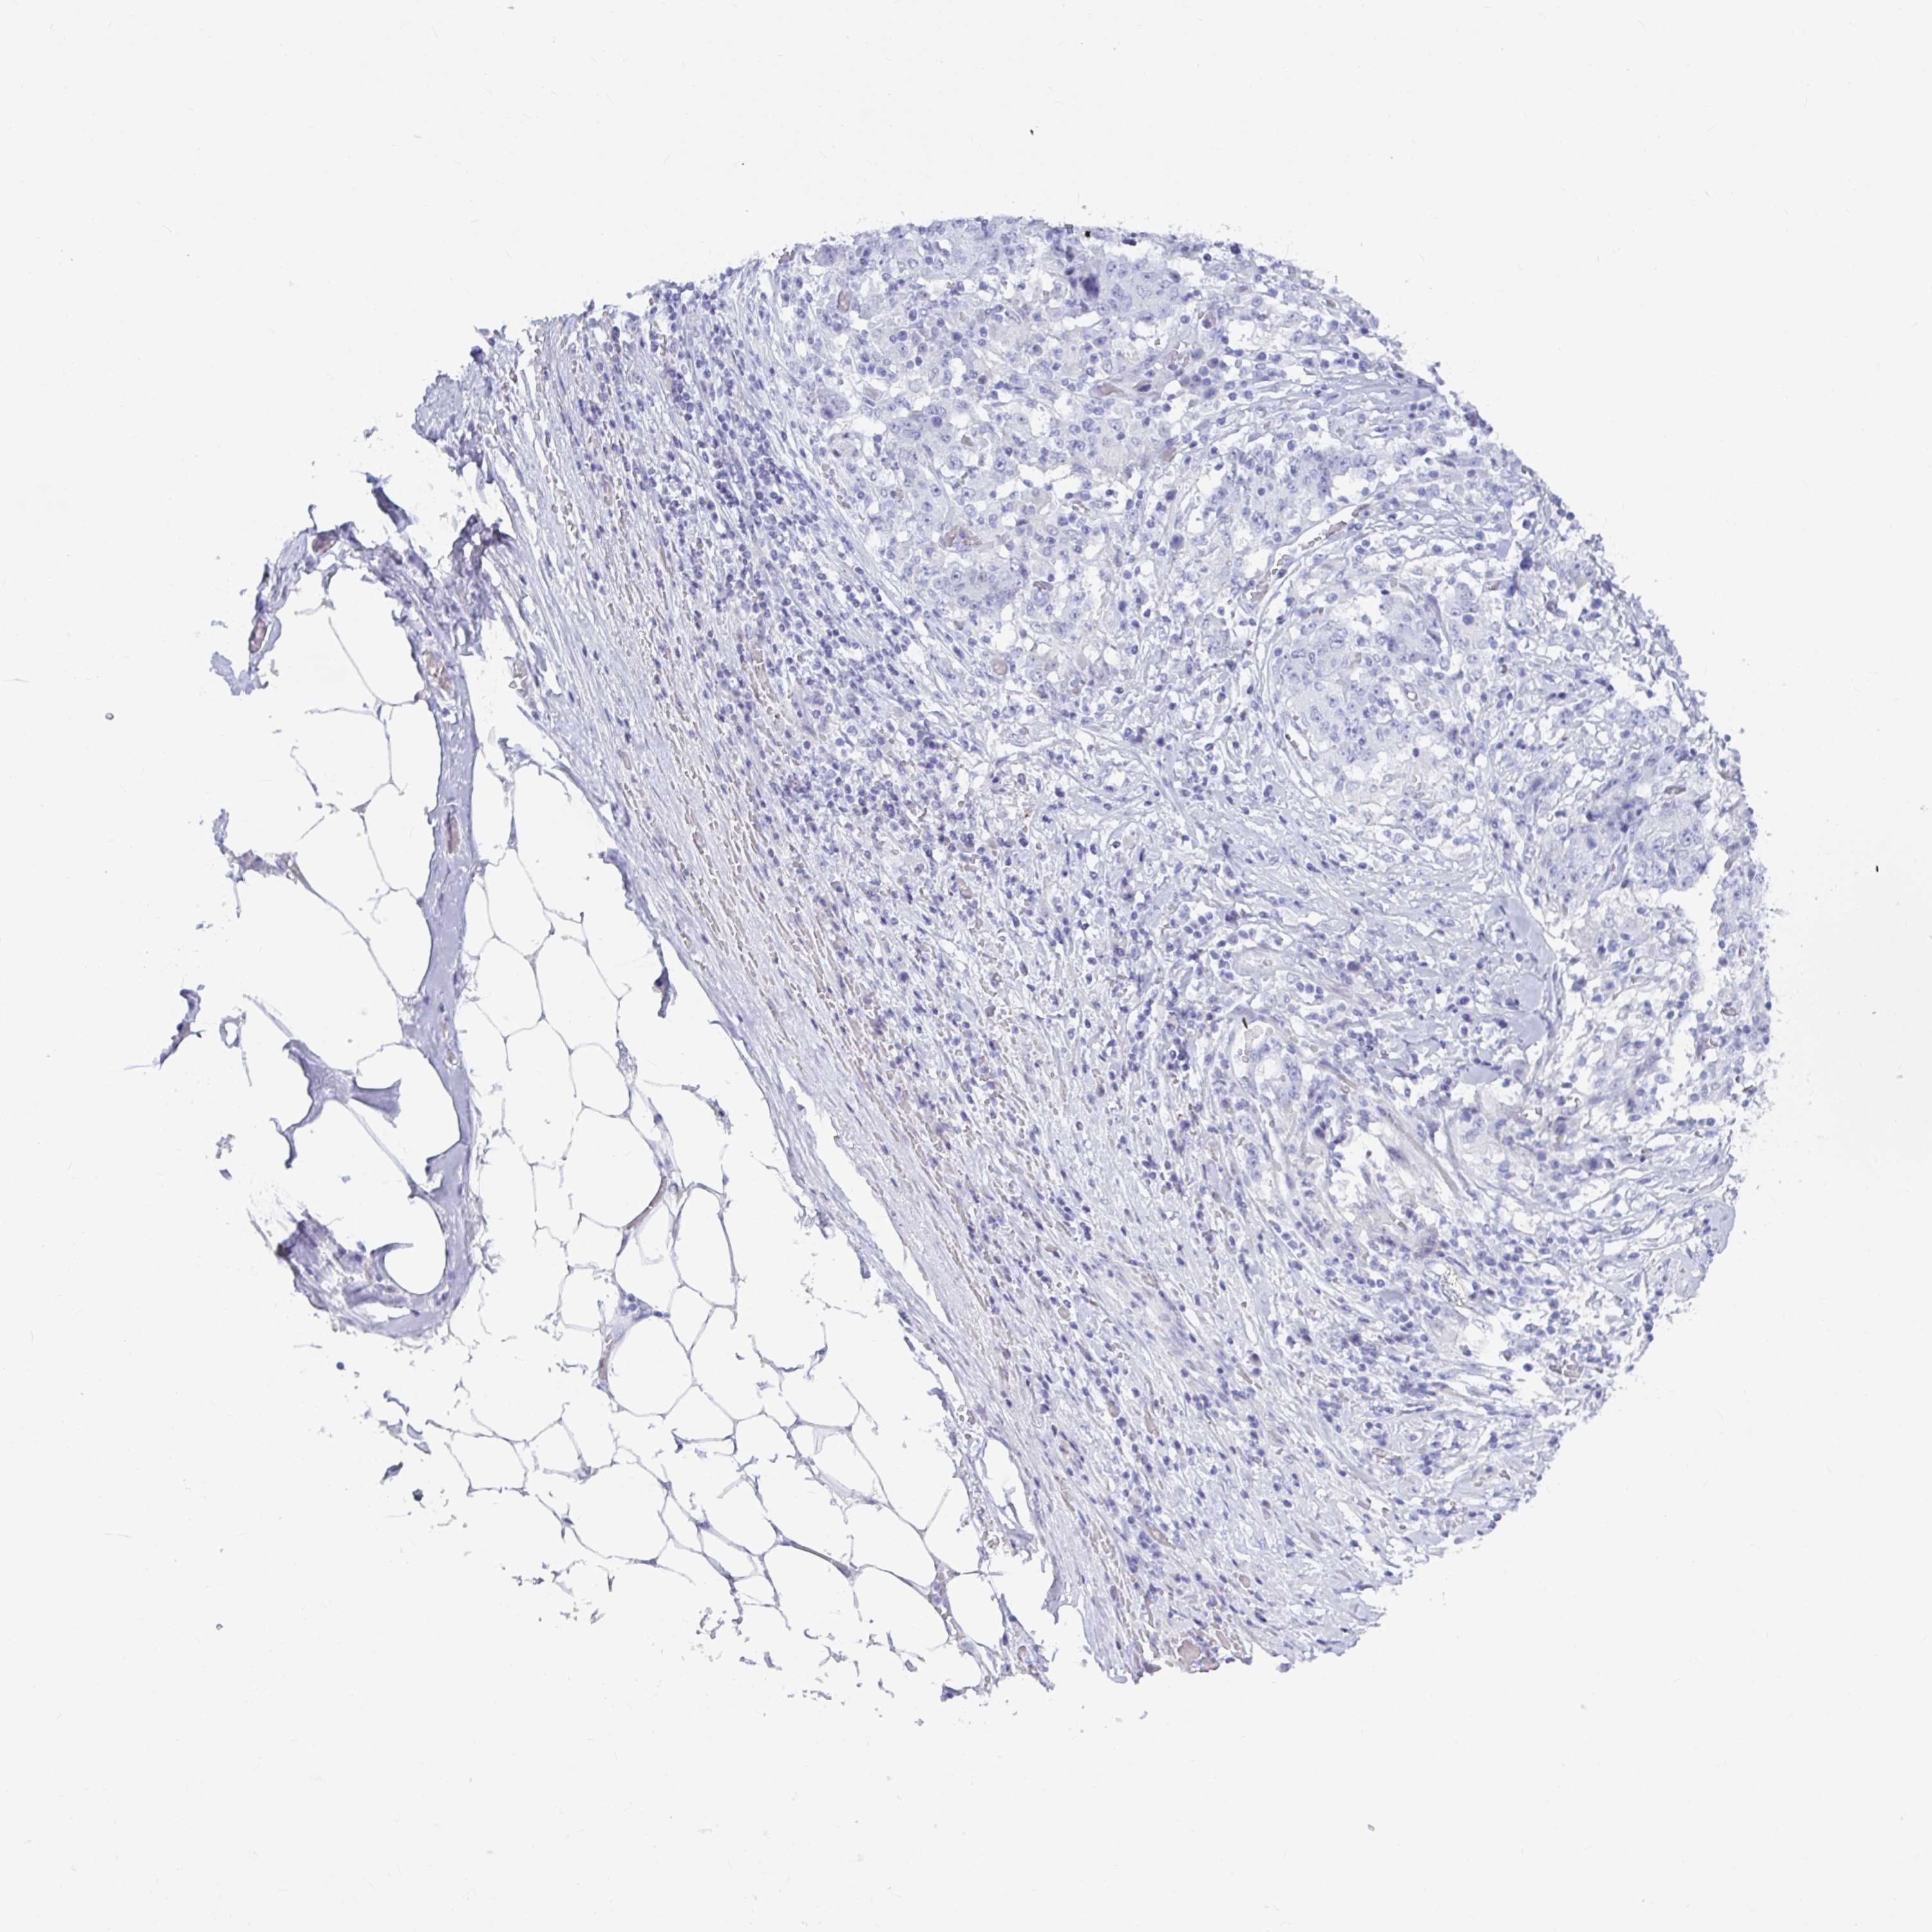

STOMACH CANCER - Protein expressioni

A mouse-over function shows sample information and annotation data. Click on an image to view it in a full screen mode. Samples can be filtered based on level of antibody staining by selecting one or several of the following categories: high, medium, low and not detected. The assay and annotation is described here.

Note that samples used for immunohistochemistry by the Human Protein Atlas do not correspond to samples in the TCGA dataset.

Antibody stainingi

Antibody staining in the annotated cell types in the current human tissue is reported as not detected, low, medium, or high, based on conventional immunohistochemistry profiling in selected tissues. This score is based on the combination of the staining intensity and fraction of stained cells.

Each image is clickable and will lead to virtual microscopy that enables deeper exploration of all samples and also displays staining intensity scores, fraction scores and subcellular localization as well as patient and tissue information for each sample.

Antibody CAB016733

Staining

High

Medium

Low

Not detected

Intensity

Strong

Moderate

Weak

Negative

Quantity

>75%

75%-25%

<25%

None

Location

Nuclear

Cytoplasmic/membranous

Cytoplasmic/membranous,nuclear

Adenocarcinoma, NOS